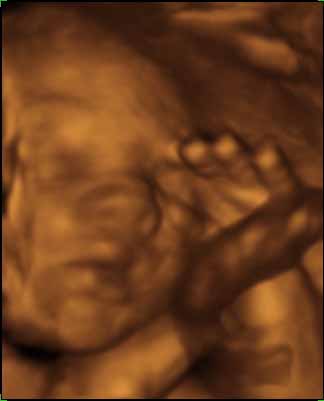

Tegnapi uhu: minden rendben - ez már nem megy olyan csoda számba... na jó, azért persze az. A doki kedves volt, úgy látszikmegérte az eddig belefektetett pénzt. Kikérdezte h mikor kell bemenni a koriba... Marcell baba feje 67mm, lábszára pedig 48. kérdeztem h mekkora lehet a súlya, azt mondta hogy azt sose akarjam tudni...